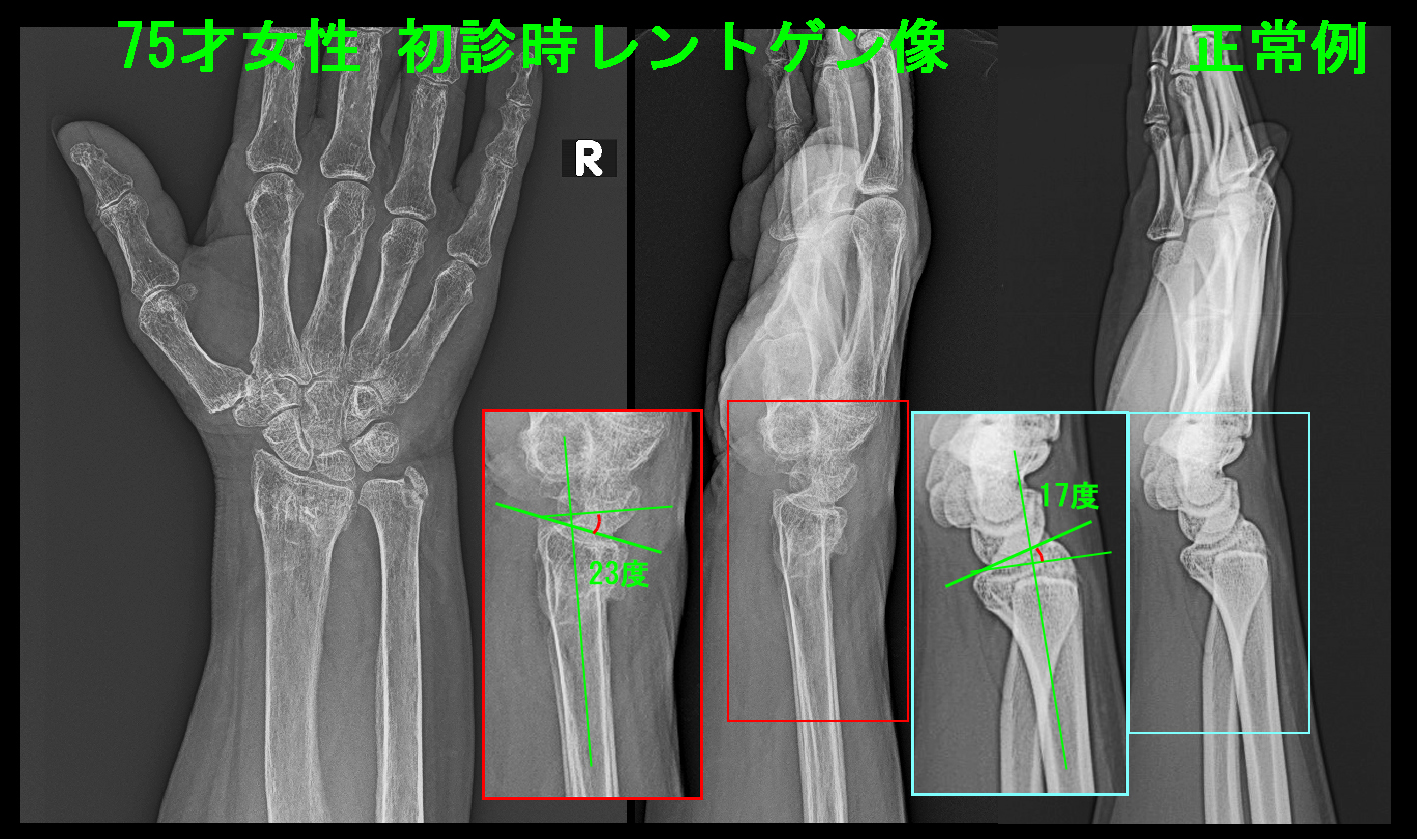

75才の女性でX年4月25日ベッドから落ちて右手をついて、右手関節の骨折(橈骨遠位端骨折)を受傷されました。

他院治療例初診時Xp.jpg

手関節の(橈骨=親指側の骨)のレントゲンの側面像では、関節面は手の甲側に23度傾斜しています。

右側の正常例では手のひら側に17度傾斜していますが、通常は15度前後とされています。

この患者さんの手関節は正常に比較すると、15度+23度=28度 手関節の傾斜が狂ってしまった状態です。

手指は28度の坂道で踏ん張っている状態ですが、人であればこれはかなり疲れる状態だと思います。

そのために右手指のこわばりが改善しないのです。